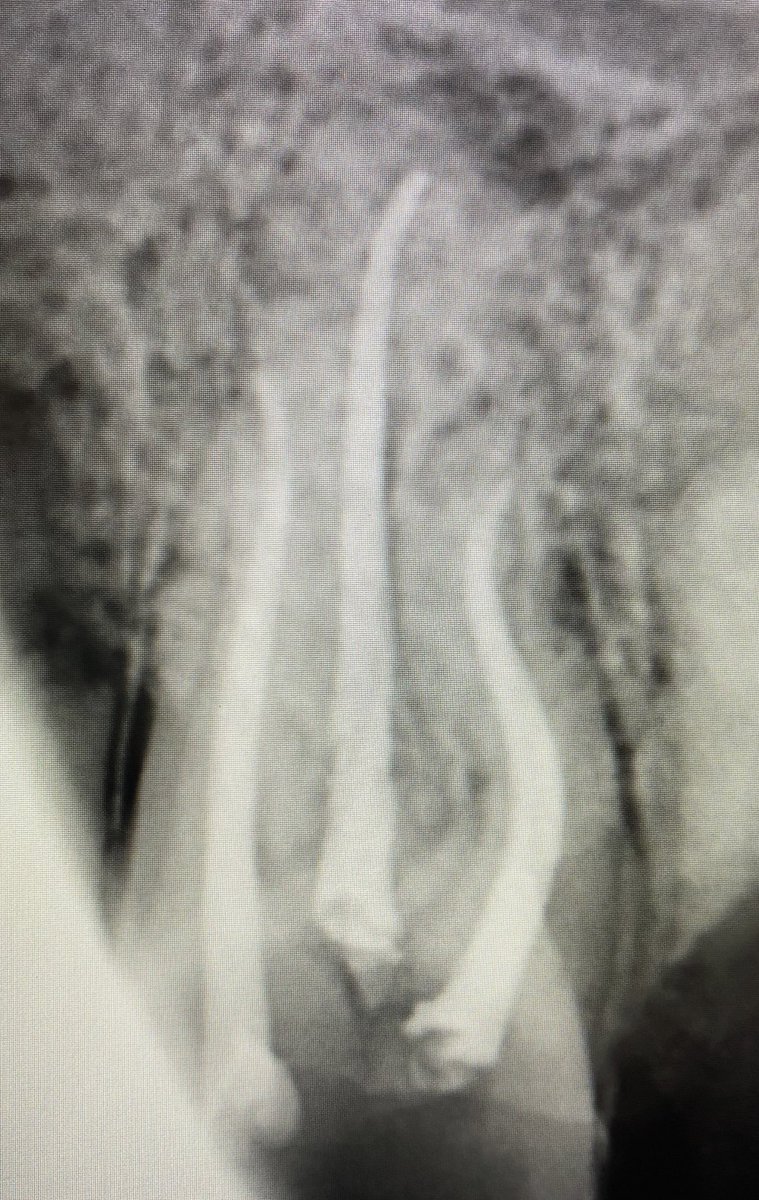

هنا يوجد. Large PA lesion

حضر المريض بضرسين مقرره للخلع من كذا عياده وابلغته انه طبعا بالامكان المحافظه عليه وتم ذلك في جلسه واحده